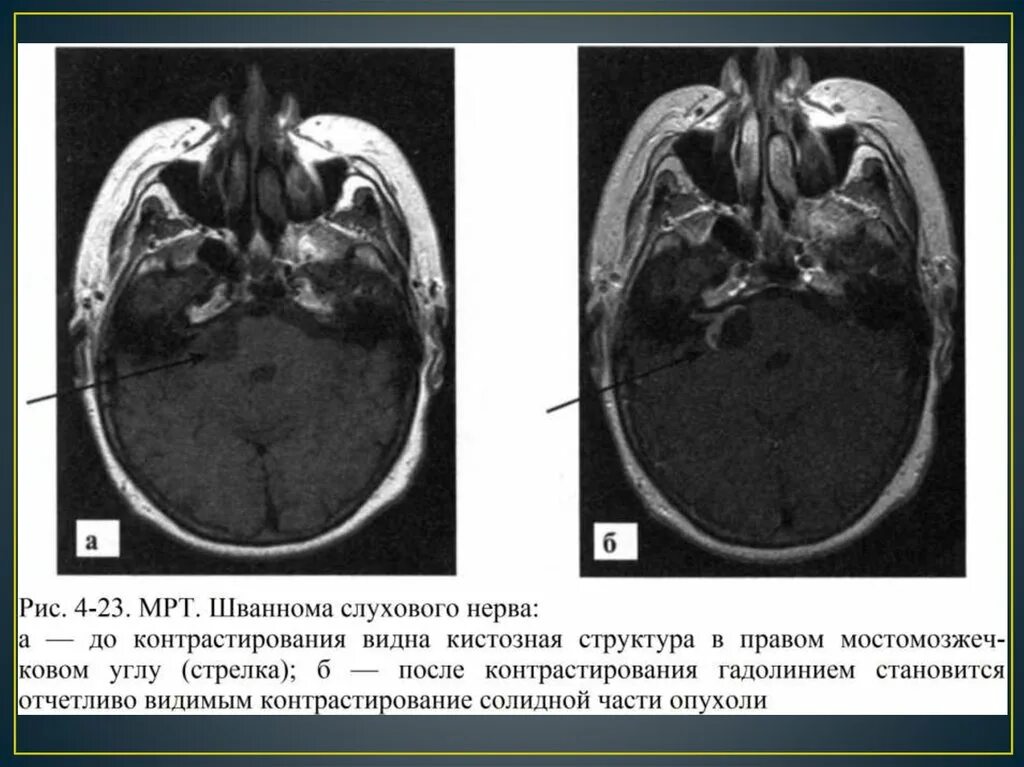

Мрт головного мозга мосто мозжечкового угла